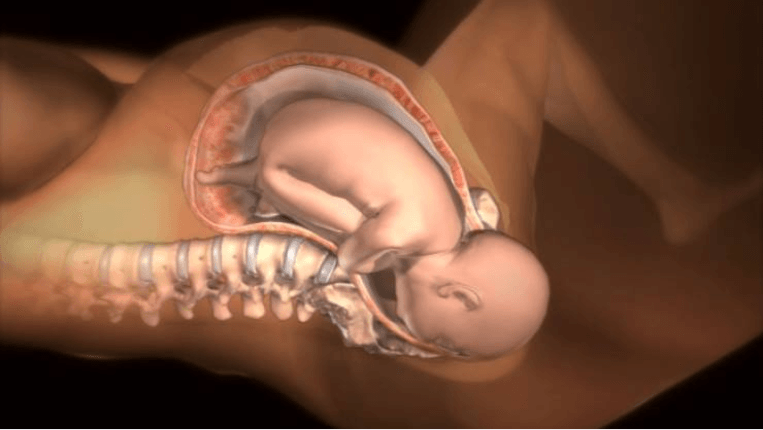

En segundo lugar, la oxitocina desempeña un papel significativo en la dilatación del cuello uterino. Las contracciones uterinas originadas por la oxitocina contribuyen a la dilatación gradual y controlada del cuello uterino, el pasaje que conecta el útero con la vagina. Esta dilatación progresiva del cuello uterino es absolutamente esencial para permitir que el bebé pueda avanzar a través del canal de parto en el momento del nacimiento.

En tercer lugar, la oxitocina es determinante en la fase final del parto al facilitar la expulsión del bebé. A medida que el cuello uterino se dilata y las contracciones uterinas se vuelven más intensas, la oxitocina desempeña un papel crucial en el impulso que guía al bebé a través del canal de parto, permitiendo que este salga del útero y entre en el mundo exterior.